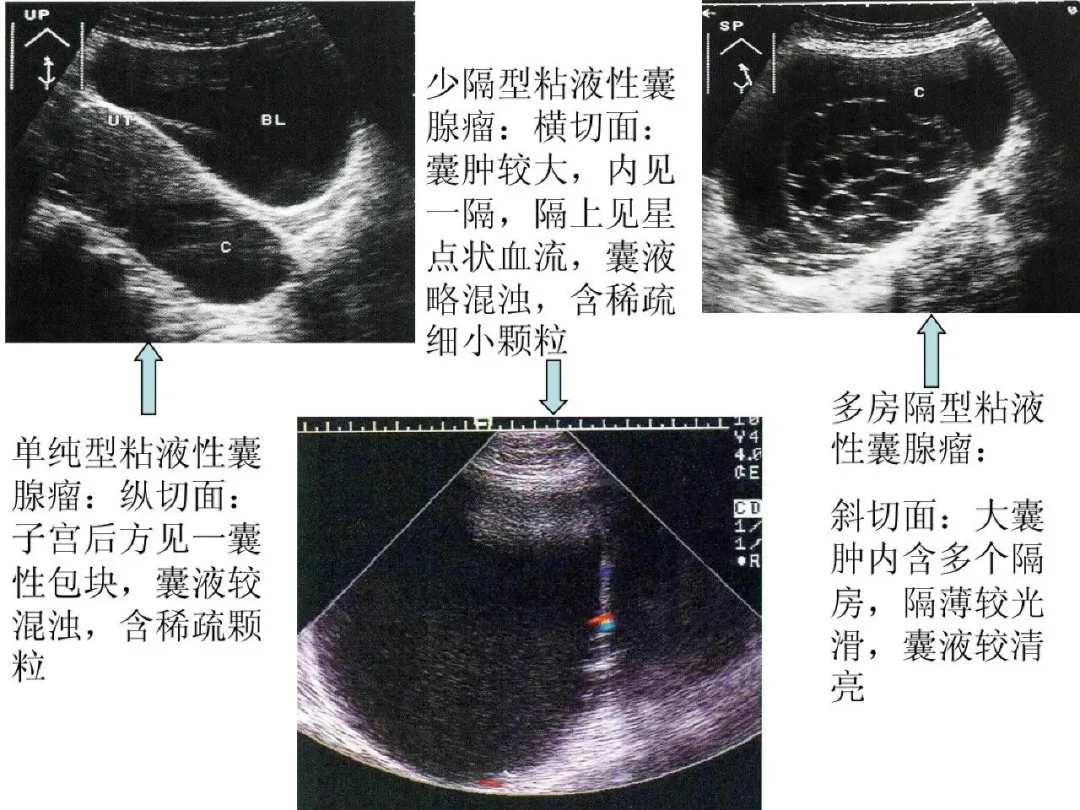

粘液性囊腺瘤

●较常见的卵巢良性肿瘤。

●二维超声图特征:大小不等,大者可达足月妊娠子宫样大小;囊壁较厚,内壁光滑;多数可见分隔,分隔或多或少,光滑,液体内显示颗粒,有的可显示梭状“胶冻体”;隔上可显示星点状血流信号。

浆液性囊腺瘤

●浆液性囊腺瘤较常见,多中等大小,单侧,可分单纯性浆液性囊腺瘤和浆液性乳头状囊腺瘤。

●二维超声图特征:呈圆形或椭圆形,单侧;壁光滑;囊液较混浊或清亮,可显示乳头状突起。